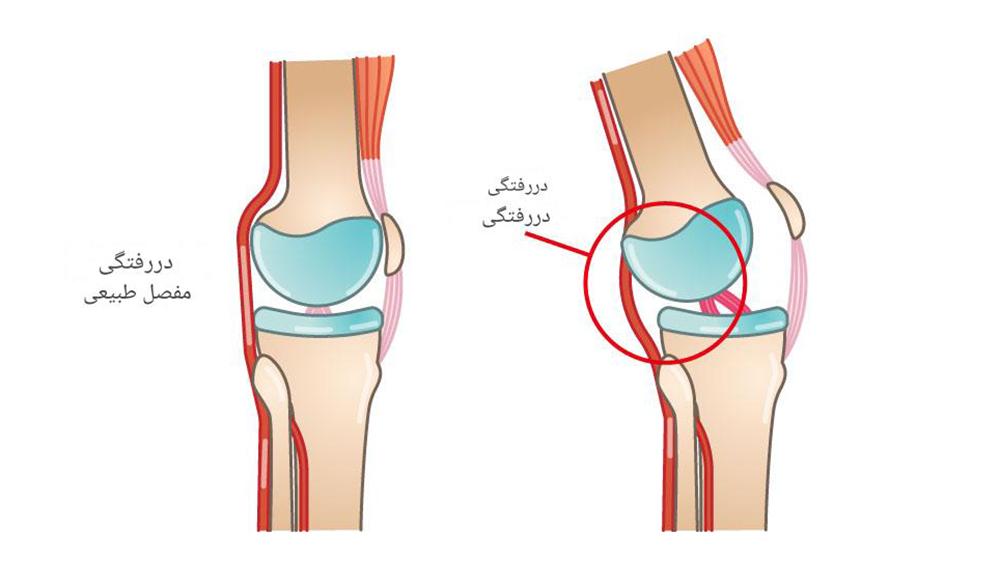

5. ناپایداری یا جابهجایی کشکک زانو

حرکت غیرطبیعی کشکک زانو (Patellar Instability) یکی دیگر از عوامل مهم است. این مشکل معمولاً به علت:

- ضربه مستقیم

- تصادفات

- آسیبهای ورزشی

- ضعف عضلات ران

- ایجاد میشود و عملکرد مفصل پاتلوفمورال را مختل میکند.

| مشکلات کشکک زانو | لقی یا جابهجایی کشکک |

- اصلاح مشکلات کشکک زانو

زمانی که آسیبهای ساختاری شدید مانند پارگی رباطها، بیثباتی قابلتوجه مفصل پیشرفته وجود داشته باشد، درمان جراحی بهترین گزینه محسوب میشود. جراحی ممکن است بهصورت آرتروسکوپی (کمتهاجمی) یا جراحی باز انجام شود تا ساختارهای آسیبدیده ترمیم یا بازسازی شوند. بازسازی رباط صلیبی به بازگرداندن ثبات زانو کمک کرده و اصلاح مشکلات کشکک باعث بهبود حرکت طبیعی مفصل میشود. در موارد پیشرفته که مفصل بهشدت تخریب شده است، تعویض مفصل زانو میتواند درد را کاهش داده و توانایی حرکت بیمار را بهطور قابلتوجهی بازیابی کند.